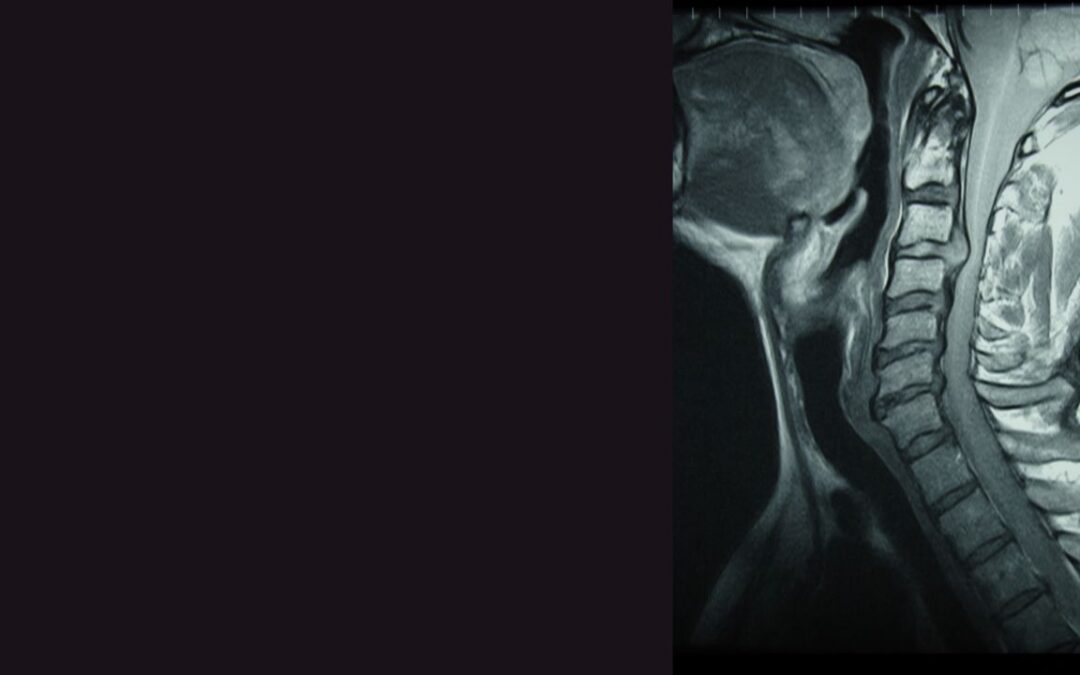

Understanding Cervical Spondylosis: How Chiropractic Care Can Offer Relief In today’s fast-paced world, many of us find ourselves spending prolonged hours at our desks, whether it’s toiling away on computers, managing paperwork, or even engaging in...

Understanding Cervical Disc Herniation: A Comprehensive Guide to Relief through Chiropractic Care Introduction: In today’s fast-paced world, many of us spend hours seated at desks or engaging in physically demanding jobs. Whether you’re an IT professional,...

Understanding Whiplash-Associated Disorders: How Chiropractic Care Can Help Introduction: Whiplash-associated disorders (WAD) are a common consequence of vehicular accidents, often resulting in significant discomfort and impairment for those affected. As professional...

Understanding and Addressing Cervicogenic Headaches: A Guide to Chiropractic Care Introduction: In today’s fast-paced world, professional individuals often find themselves burdened with various stressors, deadlines, and responsibilities. Amidst these challenges,...

Understanding Cervicalgia: A Comprehensive Guide to Chiropractic Care Introduction: Neck pain, medically termed cervicalgia, is a prevalent condition that affects countless individuals worldwide. Whether it stems from poor posture, injury, or underlying medical...